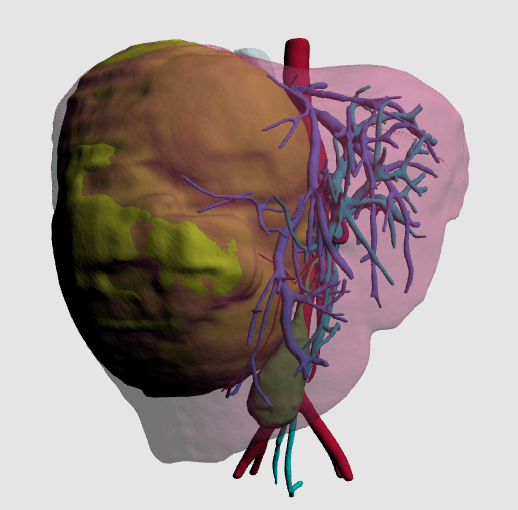

术前增强CT可见右肝巨大占位,约15x13x17cm,左肝推移,下腔静脉肝内段和中肝静脉受压,右肝静脉显示不清。

MDT讨论决定行肿瘤切除,术后行辅助化疗。手术难点:肿瘤巨大,侵犯、压迫大血管,解剖困难,术中出血风险高。对应策略:通过术前三维重建精确评估肿瘤与血管关系,制定手术计划。拟切除肿瘤所在的右半肝,剩余左半肝功能可代偿机体生理需要。

术中所见:右肝巨大占位,最大直径约20cm,肿瘤累及肝中静脉根部,侵犯右尾叶,遂行扩大右半肝切除+右尾叶切除术。手术时长6小时,出血量350ml,输注红细胞2单位。